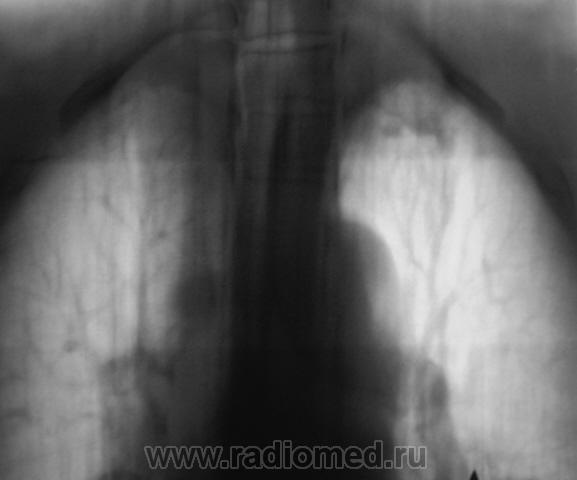

Пол пациента: Мужской пол Тип патологии: Инфекция Область исследования: Грудная клетка и верхние дыхательные пути Методы исследования: Rg При расшифровке флюорограмм пациент взят "на контроль". Известно, что на учете пациент не состоял, со слов пациента "ничем не болел". Произведено стандартное исследование - рентгенография и томография в стандартных срезах. Ваше мнение коллеги? Пнд, 23/11/2009 - 19:34 #1 Глазков Игорь А... Не на сайте Был на сайте: 1 год 2 месяцев назад Зарегистрирован: 19.12.2008 - 20:41 Публикации: 1597 инфильтративного туберкулёза слева в верхней доле Прийди к Себе

инфильтративного туберкулёза слева в верхней доле